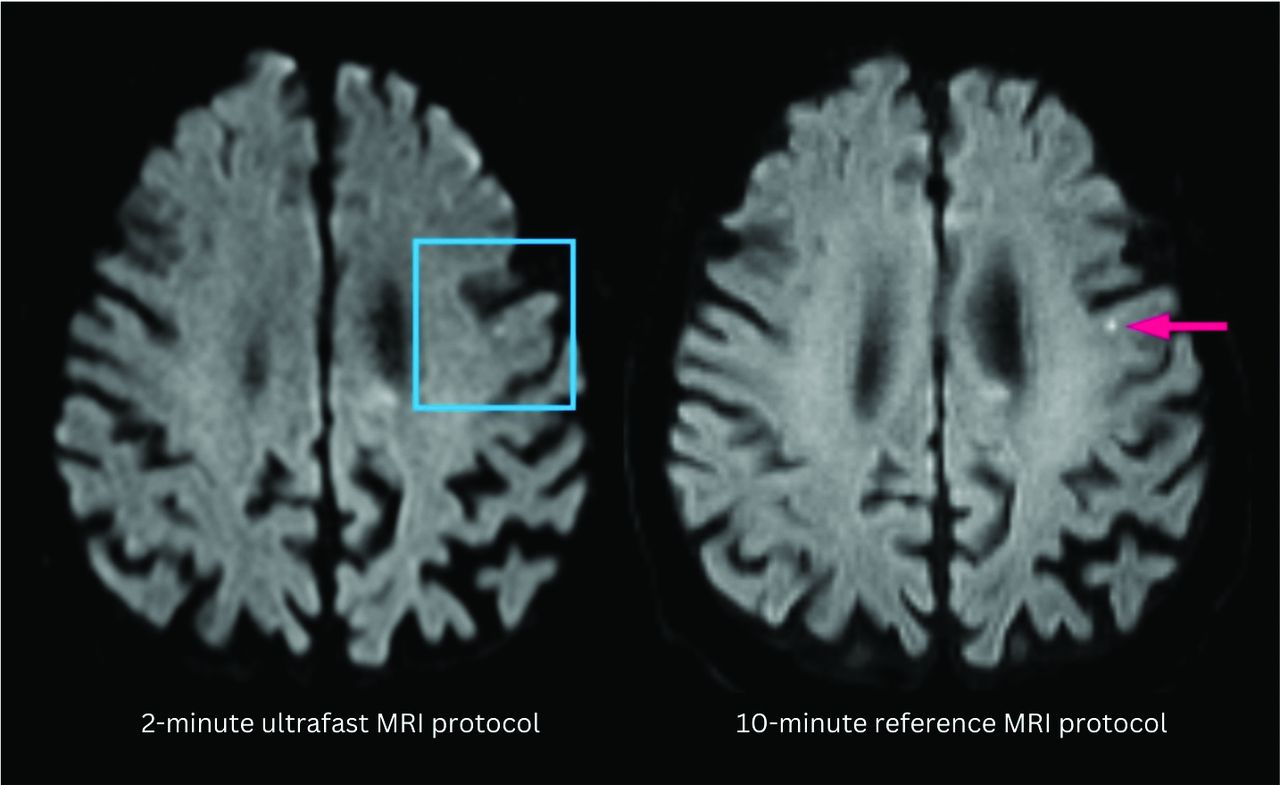

On the single case with discrepant main diagnosis by the 2 reviewing neuroradiologists, there was punctate focus of DWI hyperintensity that may represent acute to subacute infarct that was less conspicuous on the ultrafast DWI (Fig 1). After further reviewing this case with a third adjudicating neuroradiologist, the discrepancy in finding may have been due to a combination of difference in image quality between the 2 protocols and slight differences in section positioning leading to partial volume contamination as the lesion was likely smaller than the section thickness.

A punctate focus of restricted diffusion was less conspicuous on the ultrafast DWI image (left) compared with the reference DWI image (right). The decreased conspicuity may be due to a combination of differences in image quality between the 2 protocols and section positioning leading to partial volume averaging.